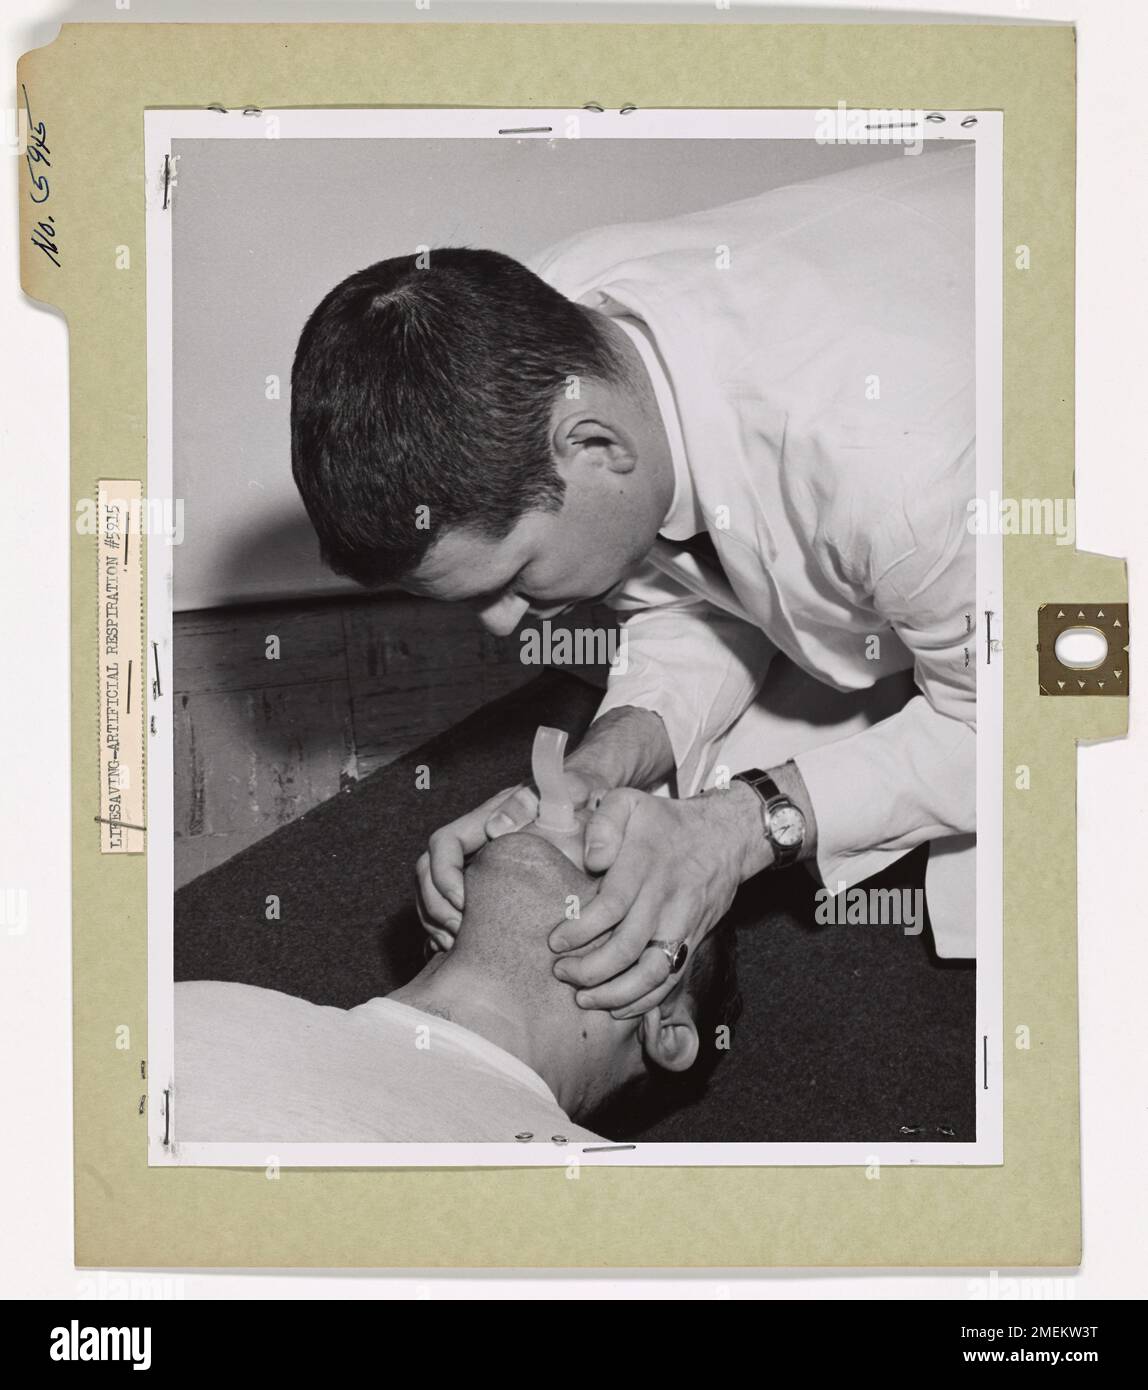

A demonstration of the proper technique for mouth-to-mouth resuscitation, highlighting the steps for opening the airway and delivering effective life-saving aid. Stock Photohttps://www.alamy.com/image-license-details/?v=1https://www.alamy.com/a-demonstration-of-the-proper-technique-for-mouth-to-mouth-resuscitation-highlighting-the-steps-for-opening-the-airway-and-delivering-effective-life-saving-aid-image508142652.html

A demonstration of the proper technique for mouth-to-mouth resuscitation, highlighting the steps for opening the airway and delivering effective life-saving aid. Stock Photohttps://www.alamy.com/image-license-details/?v=1https://www.alamy.com/a-demonstration-of-the-proper-technique-for-mouth-to-mouth-resuscitation-highlighting-the-steps-for-opening-the-airway-and-delivering-effective-life-saving-aid-image508142652.htmlRM2MEKW3T–A demonstration of the proper technique for mouth-to-mouth resuscitation, highlighting the steps for opening the airway and delivering effective life-saving aid.